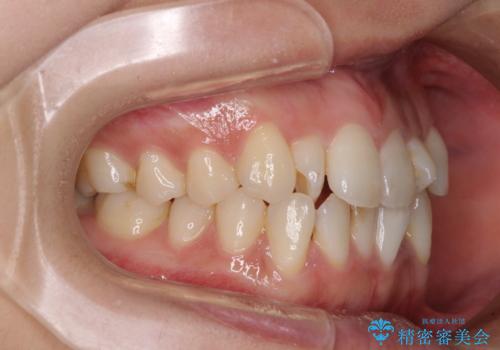

捻れた前歯をできるだけ短期間で 表側のワイヤー矯正

- 上下前歯のねじれを気にして来院された患者様です。

ワイヤー矯正でもマウスピース矯正でも対応可能でしたが、マウスピース矯正の自己管理が面倒であること、上顎前歯の捻転が著しいことから、ワイヤー矯正での治療を希望されました。